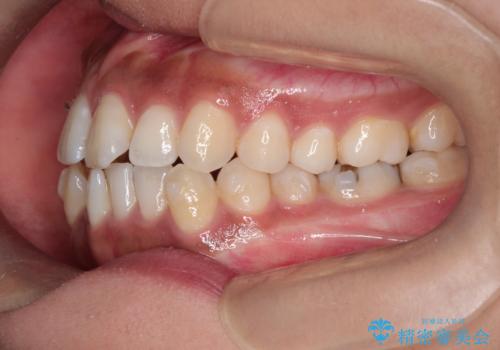

インビザラインと補助装置の併用による八重歯の抜歯矯正

- 八重歯を治したいとのことで来院されました。

重なりが強い右側の上下の歯を1本ずつ抜歯する計画としました。

インビザラインでの治療がご希望でしたが、右上の歯のかさなりが強いところは、補助装置である程度動かしてからインビザラインに移行することにしました。

下顎はインビザラインのみで治療を行いました。